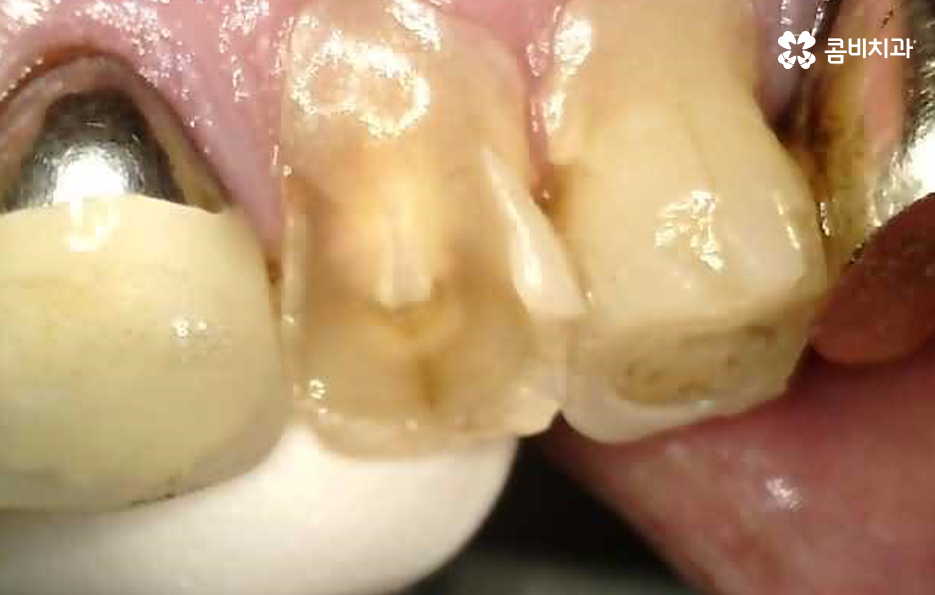

또한 60대 이후 노인 분들의 경우 치아 자체도 수명이 줄어든 상태지만 잇몸이 이미 많이 내려 앉아서 치아의 뿌리 쪽이 외부에 드러나면서 이가 시리고 흔들려서 고생하는 경우가 많을 거예요

일반적으로 50대 이전에 치아를 잃게 되는 주된 원인이 충치와 같은 치아 문제인 경우가 많다면 50대에서 60대 이후에는 치주염 뿐 아니라 충치, 치아 균열 및 오래된 보철물 등으로 인해 치아 문제가 복합적이며 전신질환이 있는 분들도 많다보니 빠른 치료 보다는 안정적이고 건강한 치료에 보다 초점을 두고 있는데요